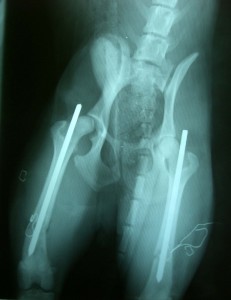

Röntgenbild nach der 1. Operation

Maui kam im Mai 2013 über den Verein Windhunde in Not zu uns. Er war als Welpe so brutal geschlagen worden, dass seine Hinterbeine mehrere Brüche aufwiesen. Tierärzte vor Ort operierten ihn. Beide Beine wurden mit Nägeln fixiert. Es folgten Knochenentzündungen. Die Nägel wurden entfernt, die kaputten Beinchen blieben steif. Als wir von seinem Schicksal erfuhren, befand er sich in einem Tierheim in Südspanien. Nach einigen Überlegungen wurde der Flug organisiert und so standen wir eines Nachts am Flughafen Wien und warteten auf unseren neuen Mitbewohner. Das, was aus der Transportbox kam, war schmutzig und stank. Doch Maui war so unwahrscheinlich fröhlich und wedelte sich förmlich in unser Leben.